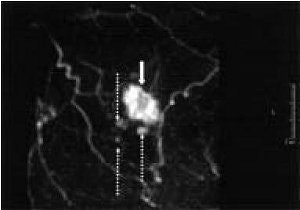

| Invasive ductal carcinoma in a 63-year-old woman. Above, ultrasound shows main tumor mass (white arrow) and satellite lesion (black arrow) with a ductal dilatation (dotted arrows) toward the nipple. The extent of intraductal component measured by ultrasound was 19 mm. Below, contrast-enhanced MRI study with maximum intensity projection (MIP) image shows main tumor (solid arrow) and satellite lesions (dotted arrows) in 3D coronal image. The extent of intraductal component measure by MRI was 18 mm. Histopathological studies diagnosed the invasive ductal carcinoma with satellite lesion and an intraductal component of 18 mm toward the nipple. |

| Sundararajan S, Tohno E, Kamm H, Ueno Ei, Minami M, "Detection of Intraductal Component around Invasive Breast Cancer Using Ultrasound: Correlation with MRI and Histopathological Findings," Radiation Medicine, Vol. 24:2, pp. 108-114, 2006, Figure 2. |